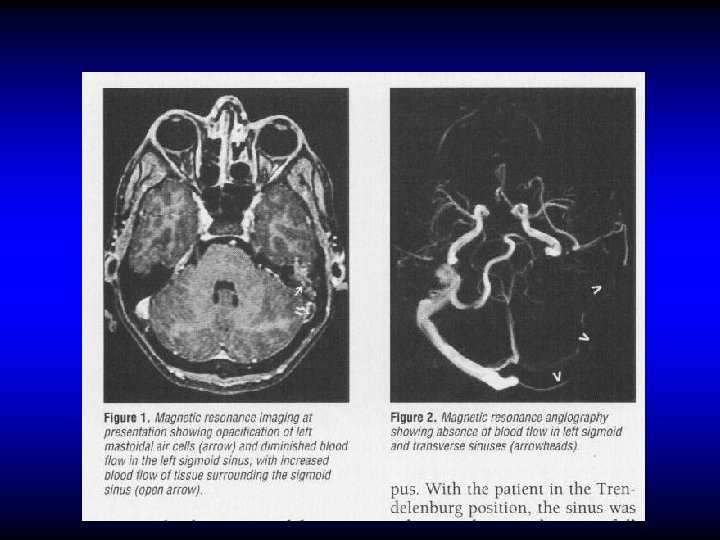

LATERAL SINUS THROMBOPHLEBITIS • • Diagnosis Fever, rigor, and sweating Headache and neck pain Tenderness and edema in the neck Manifestation of increased IC pressure Propagation and embolic manifestations Blood culture, CSF manometry CT, MRI

CT Subtraction Angiogram MRI Angiogram